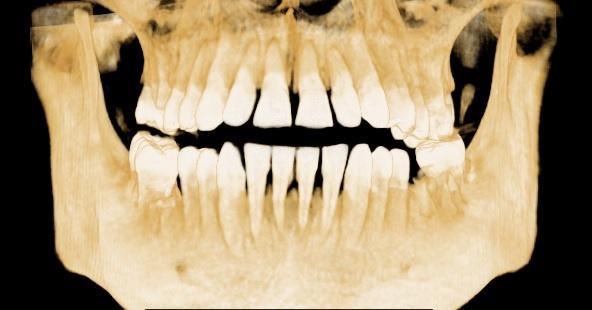

Radiografia panoramica (sinsuri si ATM) ofera o buna imagine de ansamblu,plana,globala a ambelor arcade in cadrul unei singure expuneri. Ofera informatii legate depre inaltimea procesului alveolar,informatii despre dintii prezenti, structurile anatomice invecinate,evolutia molarilor de minte, evolutia danturii la copii. In urma unei calibrari se pot efectua masuratori relative ale inaltimii osului. Acest tip de radiografie este indicata tuturor pacientilor in cadrul alcatuirii planului de tratament.